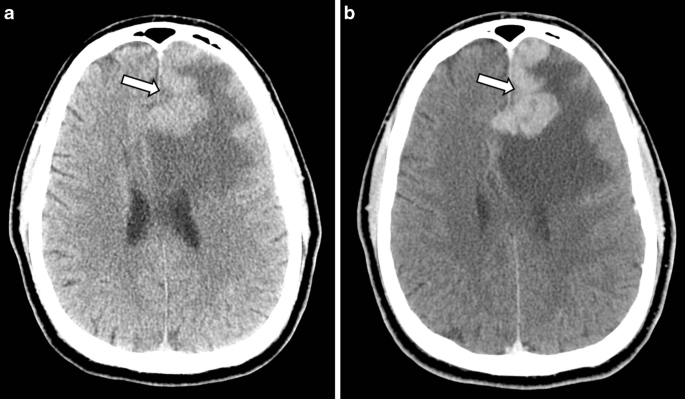

Primary Cns Lymphoma Presenting As Enhancing Cortical Ribboning And Hemorrhage Springerlink